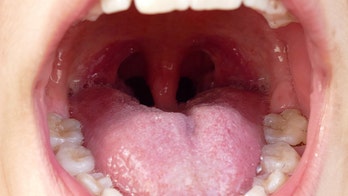

DENTAL HEALTH August 9, 2019 What are tonsil stones — and how do you know if you have them? Just one more reason your dentist was right about flossing; learn the six signs of tonsil stones and what to do about them.